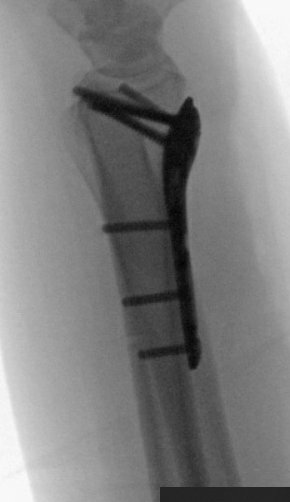

Scope assisted reduction of the articular surface was pretty cool, but radiographs honestly showed the same story

Ordinarily, I’d change that long/distal screw out, but since I was scoping the joint and didn’t see penetration, I felt ok leaving it

Debrided and pinned the SL